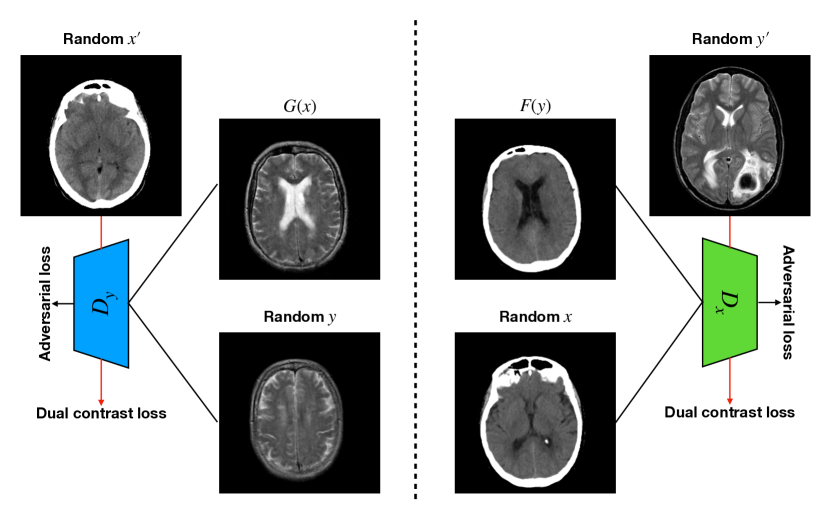

The main limitation of the above-mentioned methods is their dependency on a large number of paired images, i.e., both images belong to the same patient, perfectly registered for training [27], which is difficult to obtain. If the registration has a local mismatch between different modalities, the learning models would generate irrelevant images. To overcome this issue, Zhu et al. [49] proposed cycleGAN to synthesize images from unpaired data in an unsupervised manner. Although cycleGAN has shown remarkable results in reconstructing identical images to the real input, e.g. CT-to-CT, it can not be directly used to synthesize samples from another modality, e.g., MR-to-CT, as there are no direct constraints between real source and synthetic images [39]. For example, Zhang et al. [46] alleviated this issue using an additional loss to force the generated images to be the same as the real ones. Later, SC-cycleGAN [39] defined a structure-consistency loss into the cycleGAN. Specifically, modality-independent neighborhood descriptor (MIND) [9] and a position-based selection strategy is used as structural features and slice selection, respectively. Moreover, several studies conducted bidirectional prediction, i.e., synthesis of CT images from given MR images and vice versa [38, 1]. In addition, many cycleGAN-based methods have been proposed for medical image synthesis from unpaired data [10, 29, 3], but these methods only used the basic discriminator. The basic discriminator only utilizes images in the target domain, while we discovered that using reference images from only the target domain leads to a problem, as shown in Fig. 1 and 2.

In this paper, we propose a bidirectional learning model, known as dual contrast cycleGAN (DC-cycleGAN), for medical image synthesis from unpaired data. Specifically, a dual contrast (DC) loss is formulated that leverages the advantage of samples from the source domain as negative samples to indirectly build constraints between real source and synthetic images via discriminators, and synthesize images more related to the target domain by enforcing the synthetic images to fall far away from the source domain. In addition, structural similarity index (SSIM) [35] and cross-entropy (CE) [48] are integrated into the DC-cycleGAN structure to avoid disappearing gradient information that is caused by a mean absolute error (MAE) and synthesizing irrelevant images. SSIM considers luminance [35] and CE converges fast as its back-propagation error is less than MSE [28]. As can be seen in Figs. 1 and 2, using SSIM and CE with dual contrast can generate more clear and accurate MR images as compared with that of MAE and MSE, and SSIM and CE without dual contrast loss. Although both SSIM and CE with dual contrast and without dual contrast generate similar CT images, SSIM and CE with dual contrast quantitatively generate better images as shown in Table 4. The experimental results indicate that DC-cycleGAN is able to consider more complex features such as structure in synthesizing images and produce remarkable results as compared with other state-of-the-art methods reported in the literature.

The original discriminator aims to distinguish the real images in target domain from the synthesized images by the generator . Although using these images helps the generator to learn features from the domain, it can easily fool the discriminator by slightly changing some features of the samples from the source domain to the target domain, i.e., the discriminator identifies the synthesized image as a real one. Thus, the generator cannot learn a proper mapping in the target domain. To alleviate this issue, as shown in Fig. 4, we add an additional term, called dual contrast (DC), to leverage the advantage of samples from the source domain (see Fig. 4), as follows:

| (4) |

In this case, real images are considered class 1, and both synthesized images and samples from the source domain are considered class 0. Thus, the discriminator’s goal in our proposed method is to distinguish whether the input image belongs to class 1, i.e., real image, or class 0, i.e., synthesized image or a sample from the source domain. Adding images from the source domain as negative samples force the discriminator to guide the generator to synthesize image far away from the source domain in the latent space.

Tables 3 and 4 show the results of MR and CT synthesis, respectively. As can be seen, all components play vital role in both tables. SSIM & CE (w) performs significantly better than other losses in synthesizing MR images. This also can be seen visually in Fig. 1. In contrast, SSIM&CE (w) performs slightly better than SSIM&CE (wo) in synthesizing CT images, both generate more or less similar CT images (see Table 4).